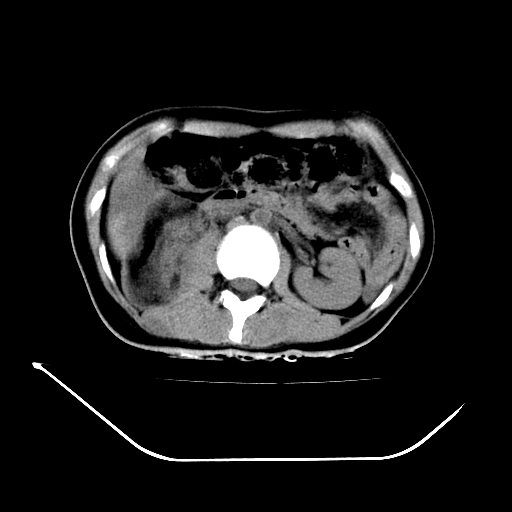

以下是引用liuyue在2008-7-19 13:02:00的发言:[br]1.肝右叶后下段及右肾挫裂伤伴腹腔积血。[br]2.右侧多发性肋骨骨折、横突骨折、右髂骨骨折伴周围软组织挫伤。[br]3.右侧腰大肌肿胀,并可见低密度影,如为气体,则肠道挫裂伤待除外。

以下是引用zhengfaming在2008-7-19 14:42:00的发言:[br]1.肝右叶后下段及右肾挫裂伤伴腹腔积血。脾脏挫裂伤待排[br]2.右侧多发性肋骨骨折、横突骨折、右髂骨骨折伴周围软组织挫伤。[br]3.右侧腰大肌肿胀,并可见低密度影,如为气体,则肠道挫裂伤待除外

以下是引用道哥在2008-7-19 16:52:00的发言:[br]肝右叶后下段及右肾挫裂伤、脾破裂伴腹腔积血。[br]2.双侧多发性肋骨骨折、横突骨折、右髂骨骨折伴周围软组织挫伤。[br]3.右侧腰大肌肿胀,并可见低密度影,如为气体,则肠道挫裂伤待除外。